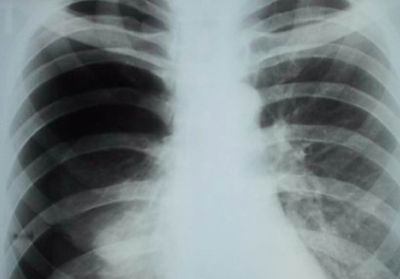

- рентгенография органов грудной клетки;

Правостороннее воспаление легкого характеризуется тупой болью в правом боку, локализованной преимущественно в подреберье.

При длительном течении заболевания боль ощущается в груди и спине со стороны пораженного органа.

- рентгенографию;